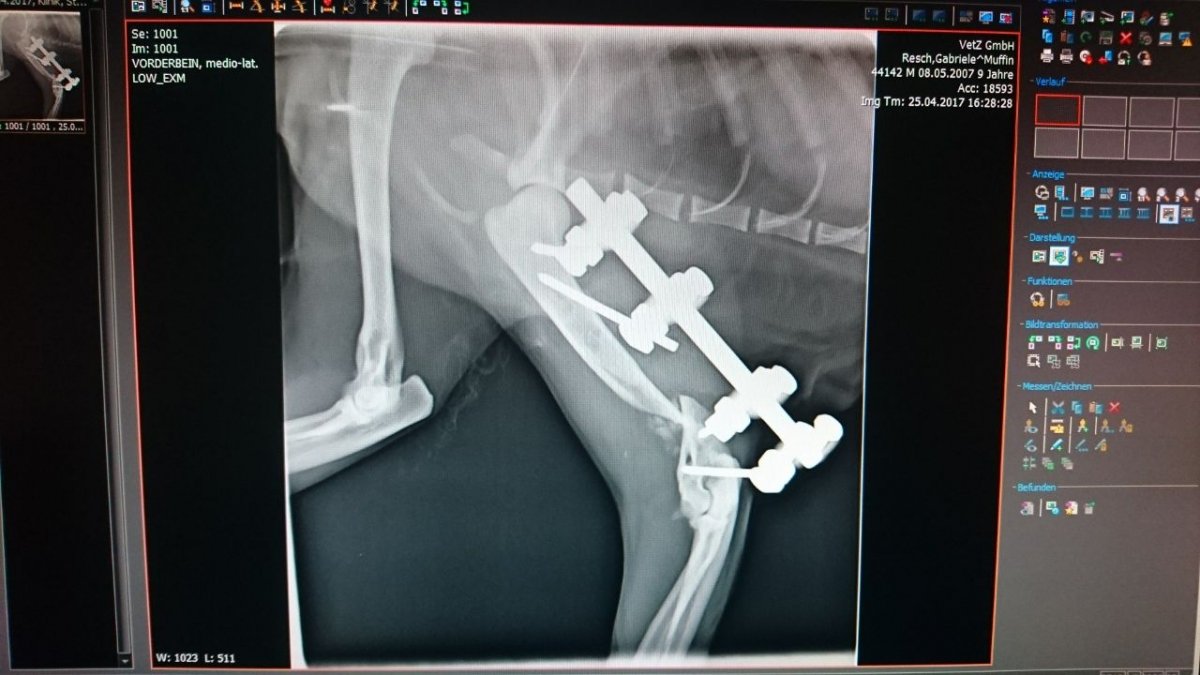

Der Trümmerbruch mit Fixateur und eingesetzter Knochenmasse aus seiner Hüfte